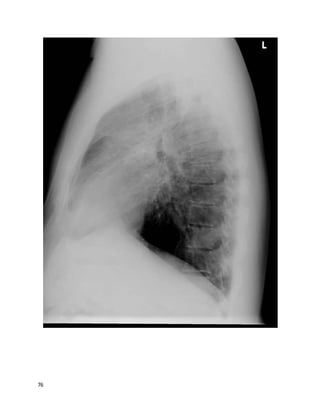

This 49 year old U.S. citizen originally from Trinidad is referred to you for

evaluation by her oncologist. She had the below chest X-ray after a mammogram

suggested abnormal lung parenchyma. Breast biopsy showed ductal carcinoma in

situ. She is to have lumpectomy soon. She has been mildly short of breath since her

20s, which has insidiously gotten worse, although she still works full-time and

takes care of 3 children. She also has a chronic dry cough worse on deep

20

inspiration. She has never sought evaluation for her symptoms and has never had

prior chest imaging. In your office, she walks 1000 feet in 6 minutes, with

desaturation from 100% on ambient air to 85% on ambulation with mild dyspnea.

A TB skin test is placed. An HIV test was negative last year.

PFTs:TLC 70% predicted (below lower limit of normal), FEV1/FVC ratio 0.65,

FEV1 2.1L (below lower limit of normal) DLCO 40% predicted, DLCO/VA 80%

predicted.

We feelthat B is the best answer.

23

Sarcoidosis is more prevalent in people of African descent, and can present at a

young age and progress insidiously. This woman likely has diffuse lung fibrosis

without hilar lymphadenopathy, so-called stage IV sarcoid. The term "stage"

misleadingly implies a predictable pattern of linear disease progression; in fact, the

radiographic pattern (stage) correlates neither with chronicity nor with changes in

pulmonary function.

Miliary TB would be expected to producea more nodular pattern on chest films, as

opposedto this linear or reticular pattern. In situ cancer would not likely have

spread lymphangitically. IPF usually preferentially affects the peripheral and basal

lungs. The small nodule in the right lung baseis probably of no significance.